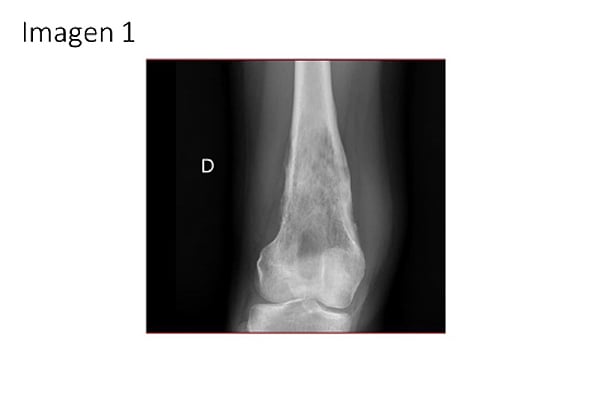

1. En un adolescente de 17 años con dolor de rodilla de tres meses de evolución, antecedente de traumatismo leve y esta radiografía, ¿cuál de las siguientes entidades debe considerarse en el diagnóstico diferencial según la clínica y la imagen radiográfica (IMAGEN 1)?: